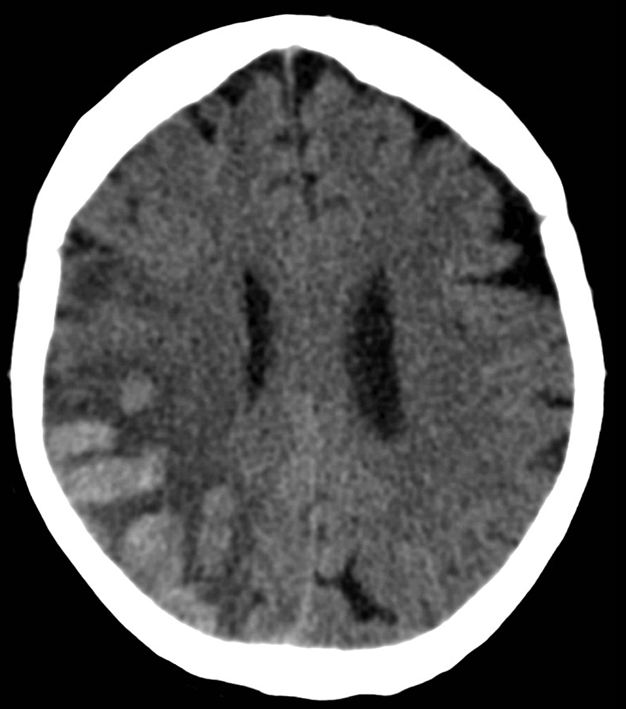

• Subdural bleeding is caused by injured bridging veins (elongation, tears) e.g. when a sudden deceleration occurs. This type of injury generally is not associated with a fracture.

5. A middle aged chronic alcoholic male. On unenhanced CT a typical crescent shape subdural hemorrhage is seen on both sides. Because of its etiology it extends across suture lines.